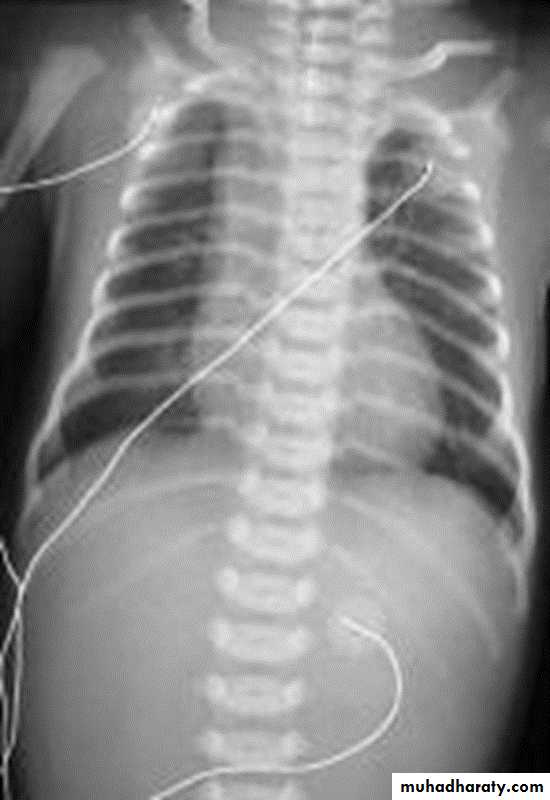

ATRESIA:

1-Complete blockage of the lumen .

2- The diagnosis is suggested after birth by inability of infant to feed or by choking during swallowing .

3- The blocked segment is mostly seen at level of thoracic inlet

TYPES OF FISTULA